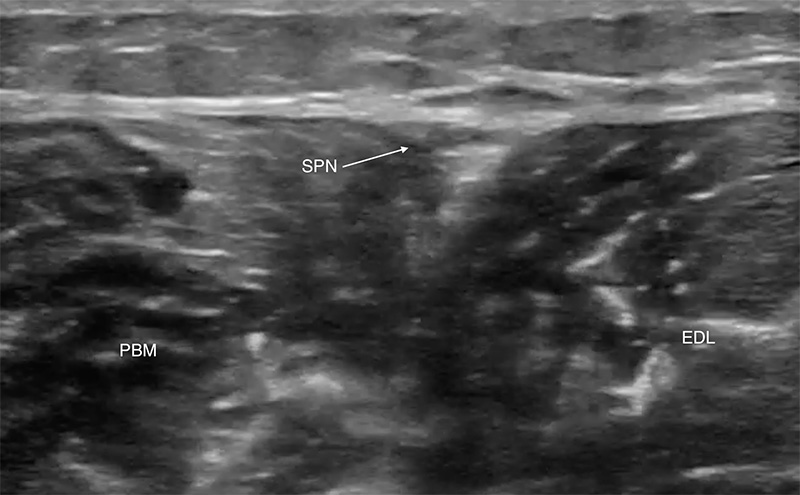

- Follow the fibula proximally to its midpoint where the peroneus brevis and extensor digitorum longus muscles are seen (Figure 1).

- These two muscles meet above the fibula.

- The superficial peroneal nerve travels in their superficial border and is seen as a hyperechoic oval or triangular shape.

Figure 1. Superficial peroneal nerve, proximal